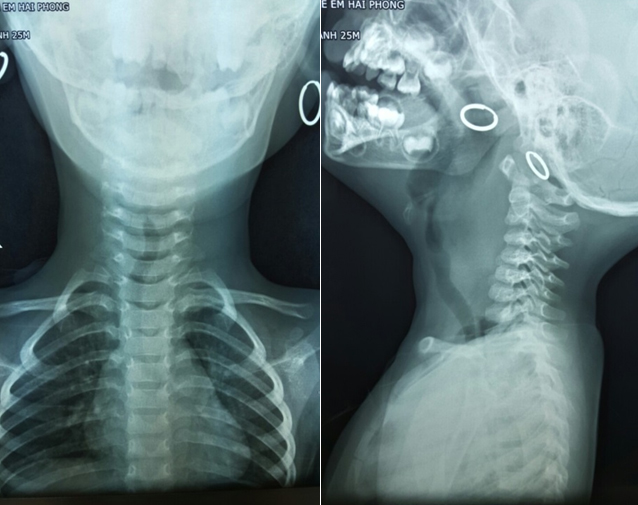

Trên phim chụp X quang cổ nghiêng thấy có một khối phồng khá lớn chèn ép vùng hạ họng và thực quản của Bệnh nhân. Trên phim cổ thẳng thấy khối phồng đẩy lệch cả khí quản.

Hình ảnh phim X quang

Đối với Bệnh nhân này trên phim X quang cho thấy khối áp xe chèn ép và đè đẩy cả vào khí quản cho nên vấn đề gây mê nội khí quản sẽ rất khó khăn, với những kinh nghiệm về chuyên khoa nhi các bác sĩ đã phối hợp cấp cứu thành công cho Bệnh nhân.